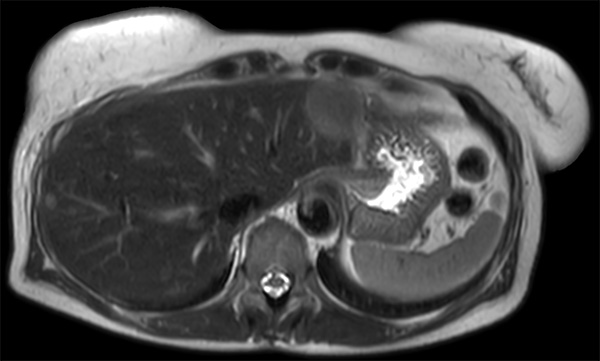

Patient with multiple liver lesions showing up hyperintense on T2-weighted images. The high spatial resolution of MultiVane XD can be appreciated by comparing the images demonstrating the two hyperintense focal liver lesions. mDIXON Quant was performed for quantification of intralesional and hepatic parenchymal fat content. The fat content in the liver parenchyma was normal. The lesion has a fat fraction of 25-30%. Histopathologic diagnosis was hepatocellular adenoma.